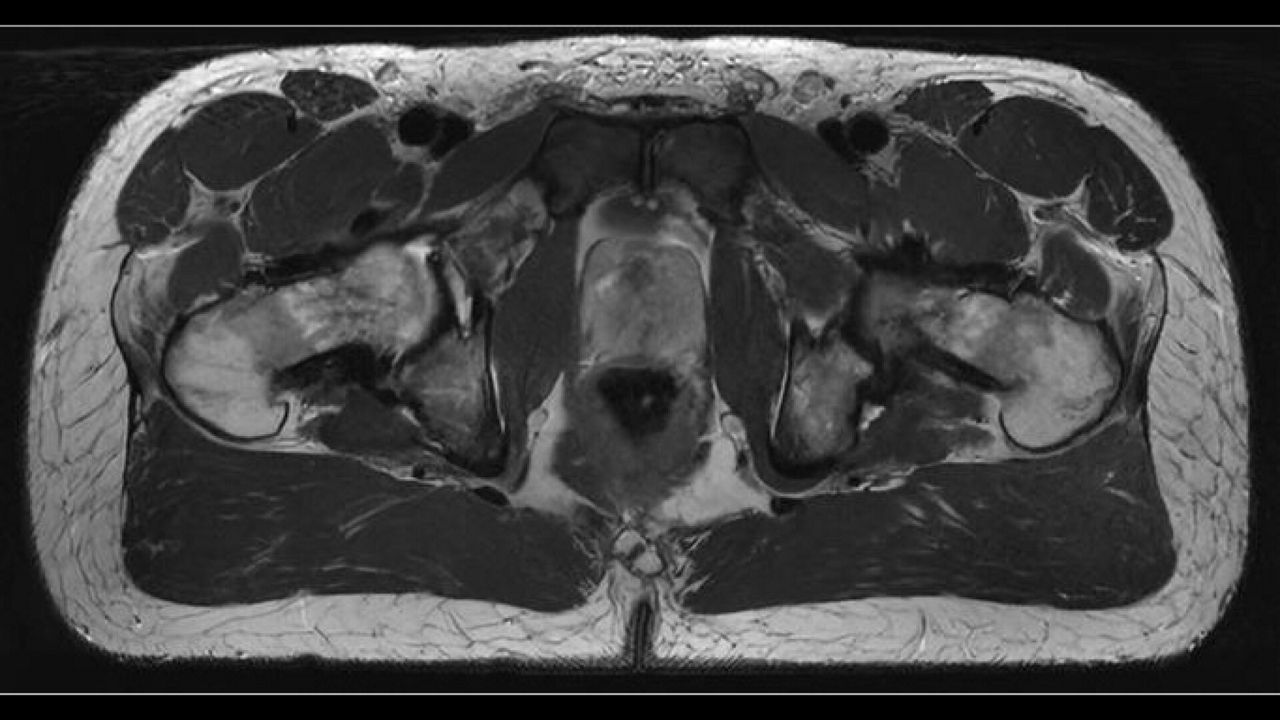

AIR™ RT Suite is easy to setup and ensures the proper positioning of patients. The 32-channel, AIR™ Open Coils deliver a high signal-to-noise ratio (SNR) and when combined with AIR™ Recon DL, our deep-learning based reconstruction algorithm, you can expect up to 60% sharper images.

AIR™ RT Suite is compatible with iRT MR Direct and MRI planner, Spectronic Medical’s deep-learning-based pseudo-CT solution, which provides visualization of fiducial markers for position verification. It is also compatible with MR Contour DL, a deep learning-enabled auto organs-at-risk (OARs) segmentation solution for radiation therapy planning.